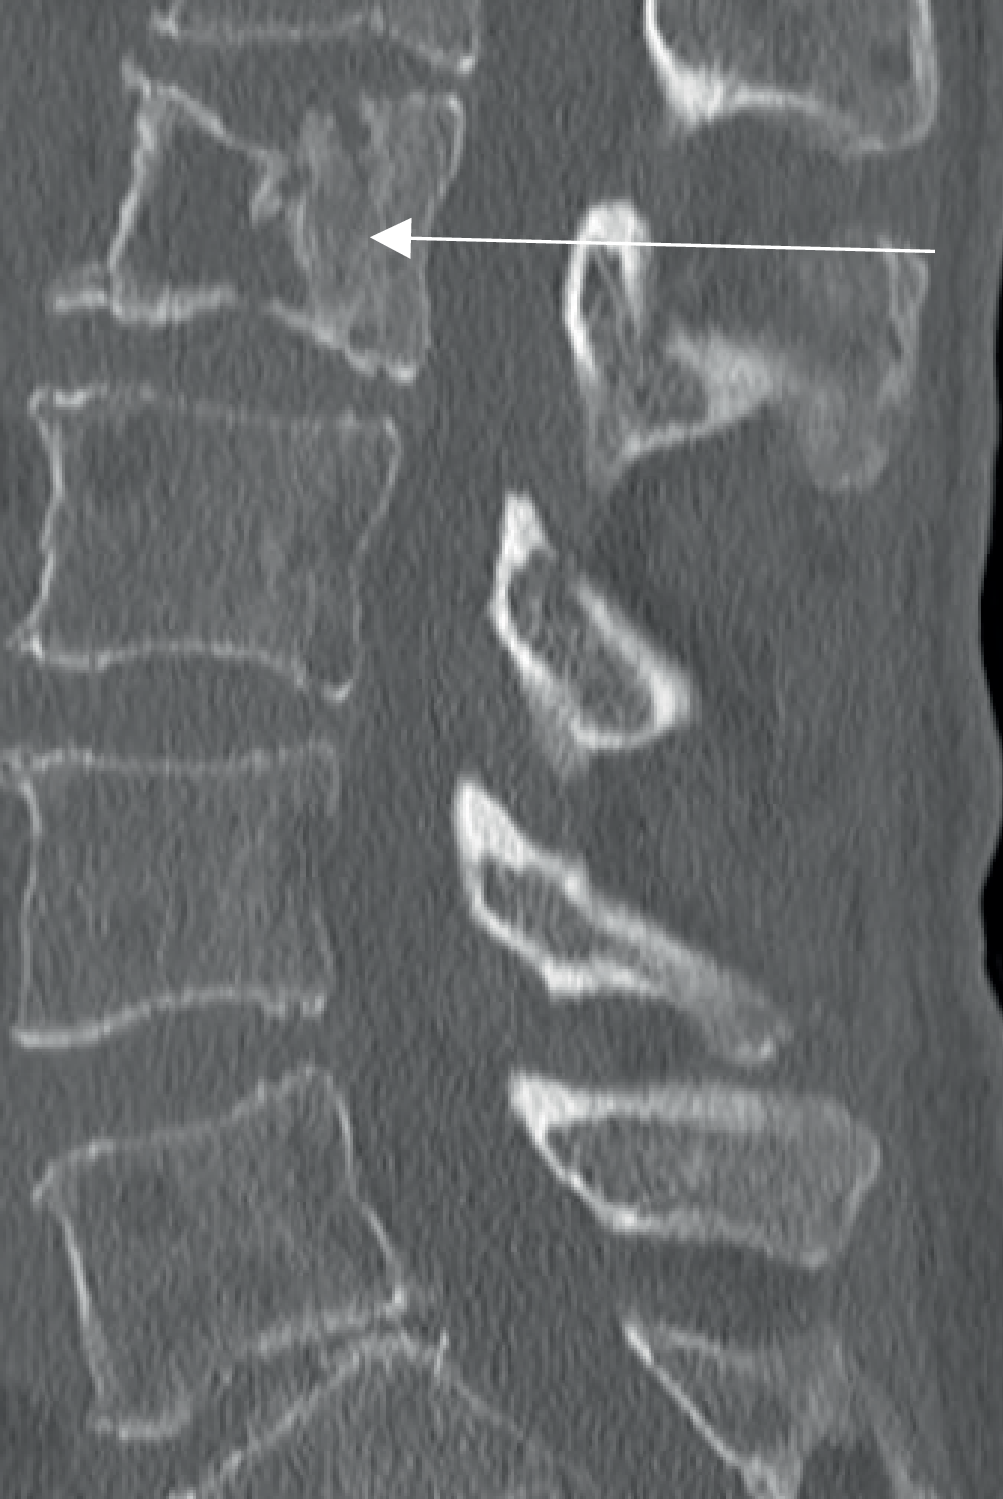

Eine 69-jährige Patientin wird mit immobilisierenden Rückenschmerzen in die Notaufnahme eingeliefert (Abb. 1). Sie sei über eine Teppichkante gestolpert, dann habe sie sich nicht mehr bewegen können.

Computertomographisch erkennbare Wirbelkörperfraktur mit Deckplatteneinbruch (Pfeil) bei insgesamt multiplen ossären Läsionen [1]. (Aus [4])